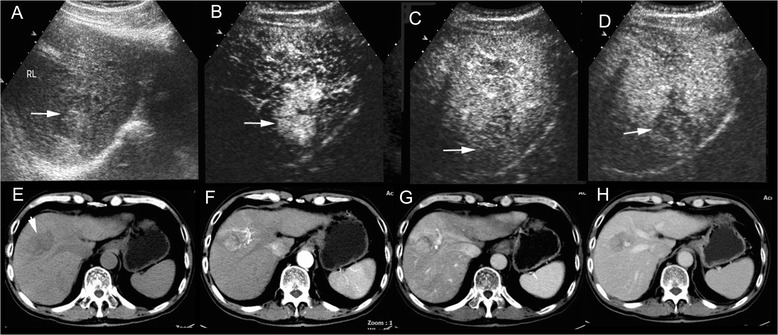

Fig. 1.

cHCC-CC in a patient with chronic hepatitis B. Simultaneous elevation of AFP (718 ng/ml) and CA19-9 (45.0U/ml) was detected in the patient. Unenhanced ultrasound shows a hypoechoic mass of 4.6 cm in right lobe of the liver (a, arrow). The mass displays heterogeneous hyperenhancement in the arterial phase (b, 26 s after contrast agent injection) followed by quick (c, 58 s after injection) and marked washout (d, 102 s after injection) in the portal phase on CEUS, resembling the enhancement pattern of intrahepatic cholangiocarcinoma. Unenhanced CT scan reveals a hypodense mass in right lobe of the liver (e, arrow). The mass displays heterogeneous hyperenhancemen in the arterial phase (f, arrow) followed by washout (g) in the portal phase and the late phase (h) on contrast-enhanced CT, resembling the enhancement pattern of HCC